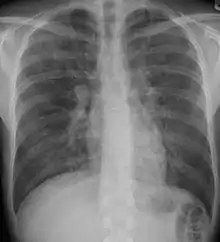

A chest X-ray demonstrating pulmonary fibrosis due to amiodarone